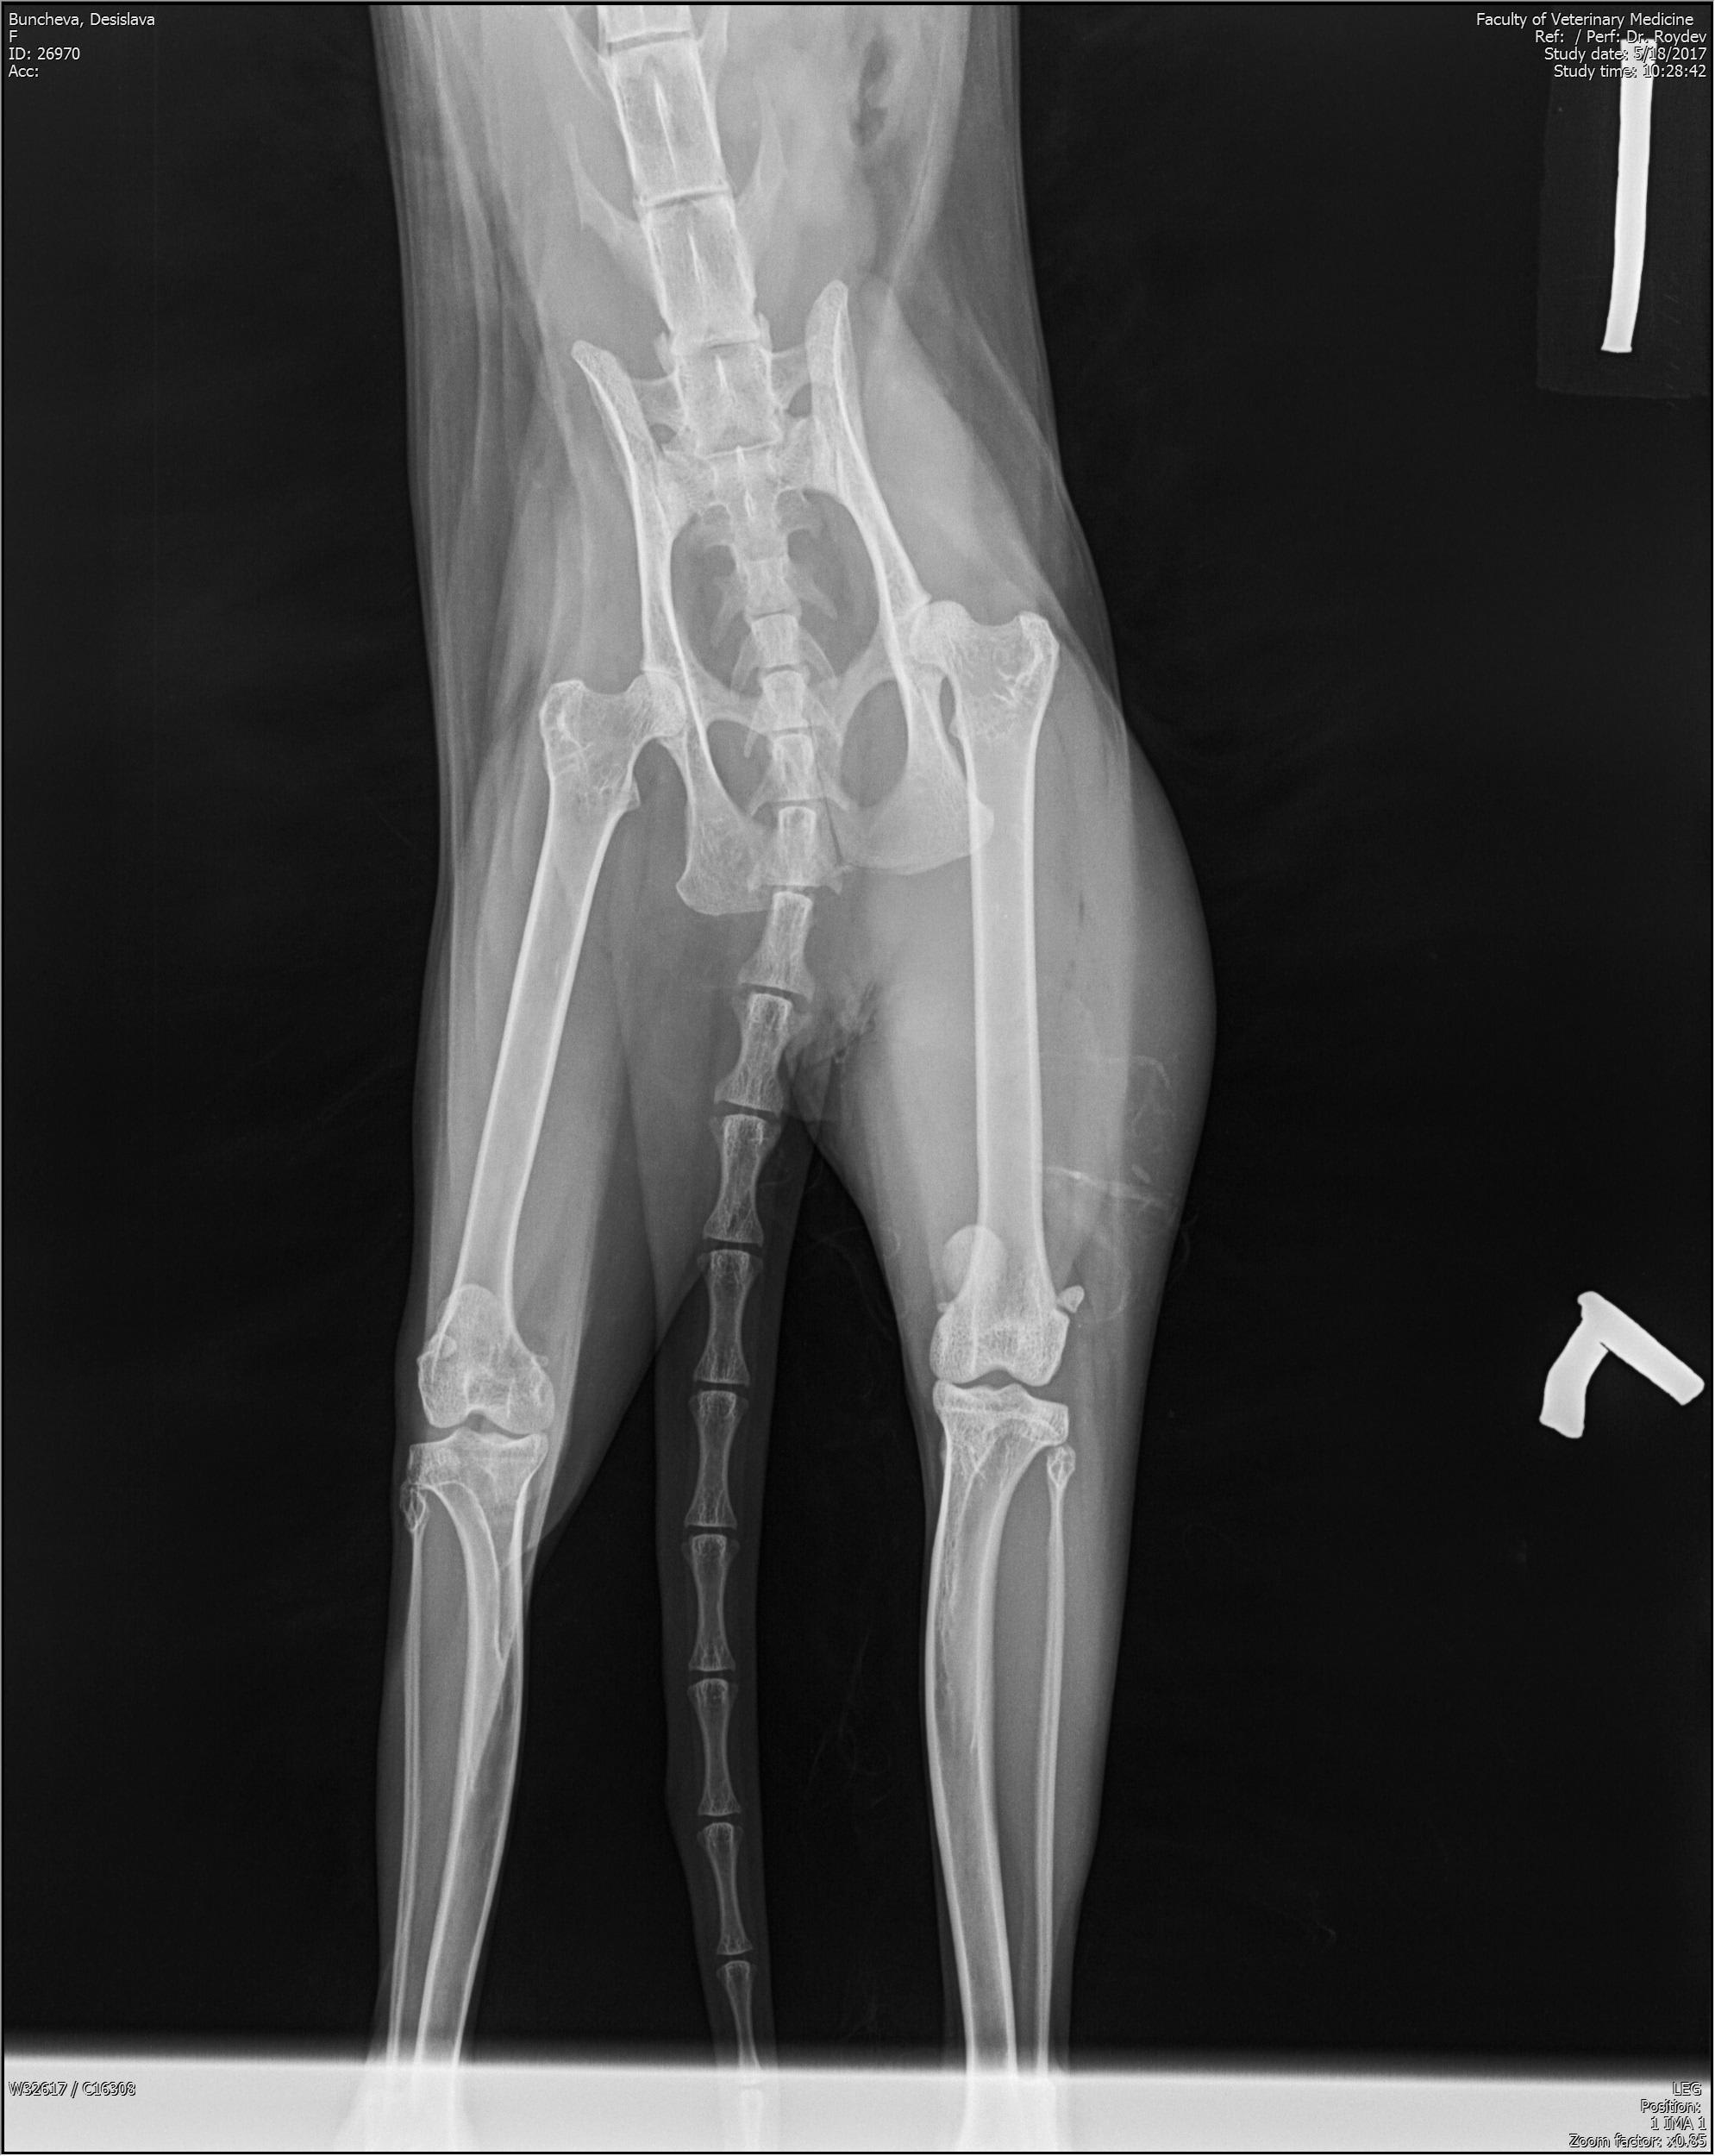

Hello, for about 6 months ago started to limb with her back right foot, when walking. We went to various doctors. For 1 month and a half she keeps her sick leg high in the air. Doctors think it is a tumor and we need to remove her leg. We don't have any bio tests done, only pictures. She is two years old. Can you tell from the pictures if it is a tumor and if so, are there alternatives?

It does look very suspicious for a tumour, a biopsy could be performed to confirm what is the underlying nature prior to amputation, referral to a veterinary university or specialist oncologist would ensure all options are fully explored for Audrey